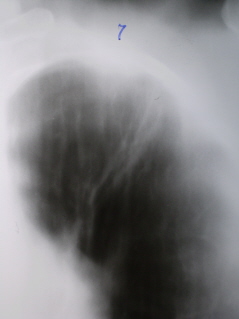

Перисциссурит – это вариант инфильтративного поражения лёгкого, при котором процесс локализуется в верхней доле вдоль междолевой щели, занимая частично 2 – 3 сегмента. Нижняя граница тени прилежит к междолевой плевре, поэтому чётко отграничена, а верхняя нечеткая, размытая (иллюстрации 16, 17). Так же, как и при других вариантах инфильтративного туберкулёза может наблюдаться распад.

4. Перисциссурит - обширная инфильтративная тень с наличием с одной стороны четкого края, с другой - размытого. Такой характер тени определяется поражением 1-2 сегментов, располагающихся вдоль междолевой борозды (рис. 6.9). Нередко отмечается также поражение междолевой плевры, иногда с накоплением выпота. Так же как и при других вариантах, может быть распад.

(a) - Перисциссурит, или краевой инфильтрат – это облаковидный инфильтрат, расположенный у междолевой борозды.Вершина треугольника обращена к корню легкого, основание – кнаружи. Верхние границы расплывчаты и переходят без резких очертаний в малоизмененную легочную ткань. Нижняя граница соответствует междолевой плевре и поэтому четкая.